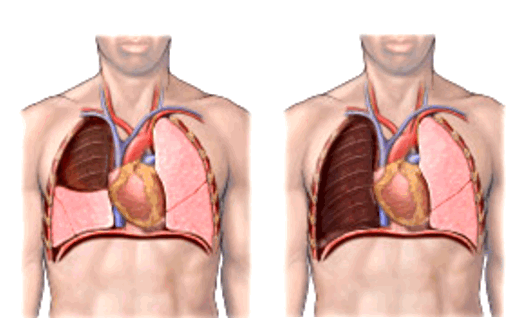

Фото 3 — Лобэктомия

Фото 4 — Пневмонэктомия

Хирургическое удаление опухоли зачастую является основным видом лечения локального рака бронхов и легких, когда отсутствуют отделанные метастазы. Цель радикальной операции — полностью удалить опухолевую ткань. В зависимости от размеров и расположения очагов, прибегают к разным видам хирургических вмешательств:

- Удаление всего легкого — пульмонэктомия.

- Удаление доли легкого — лобэктомия.